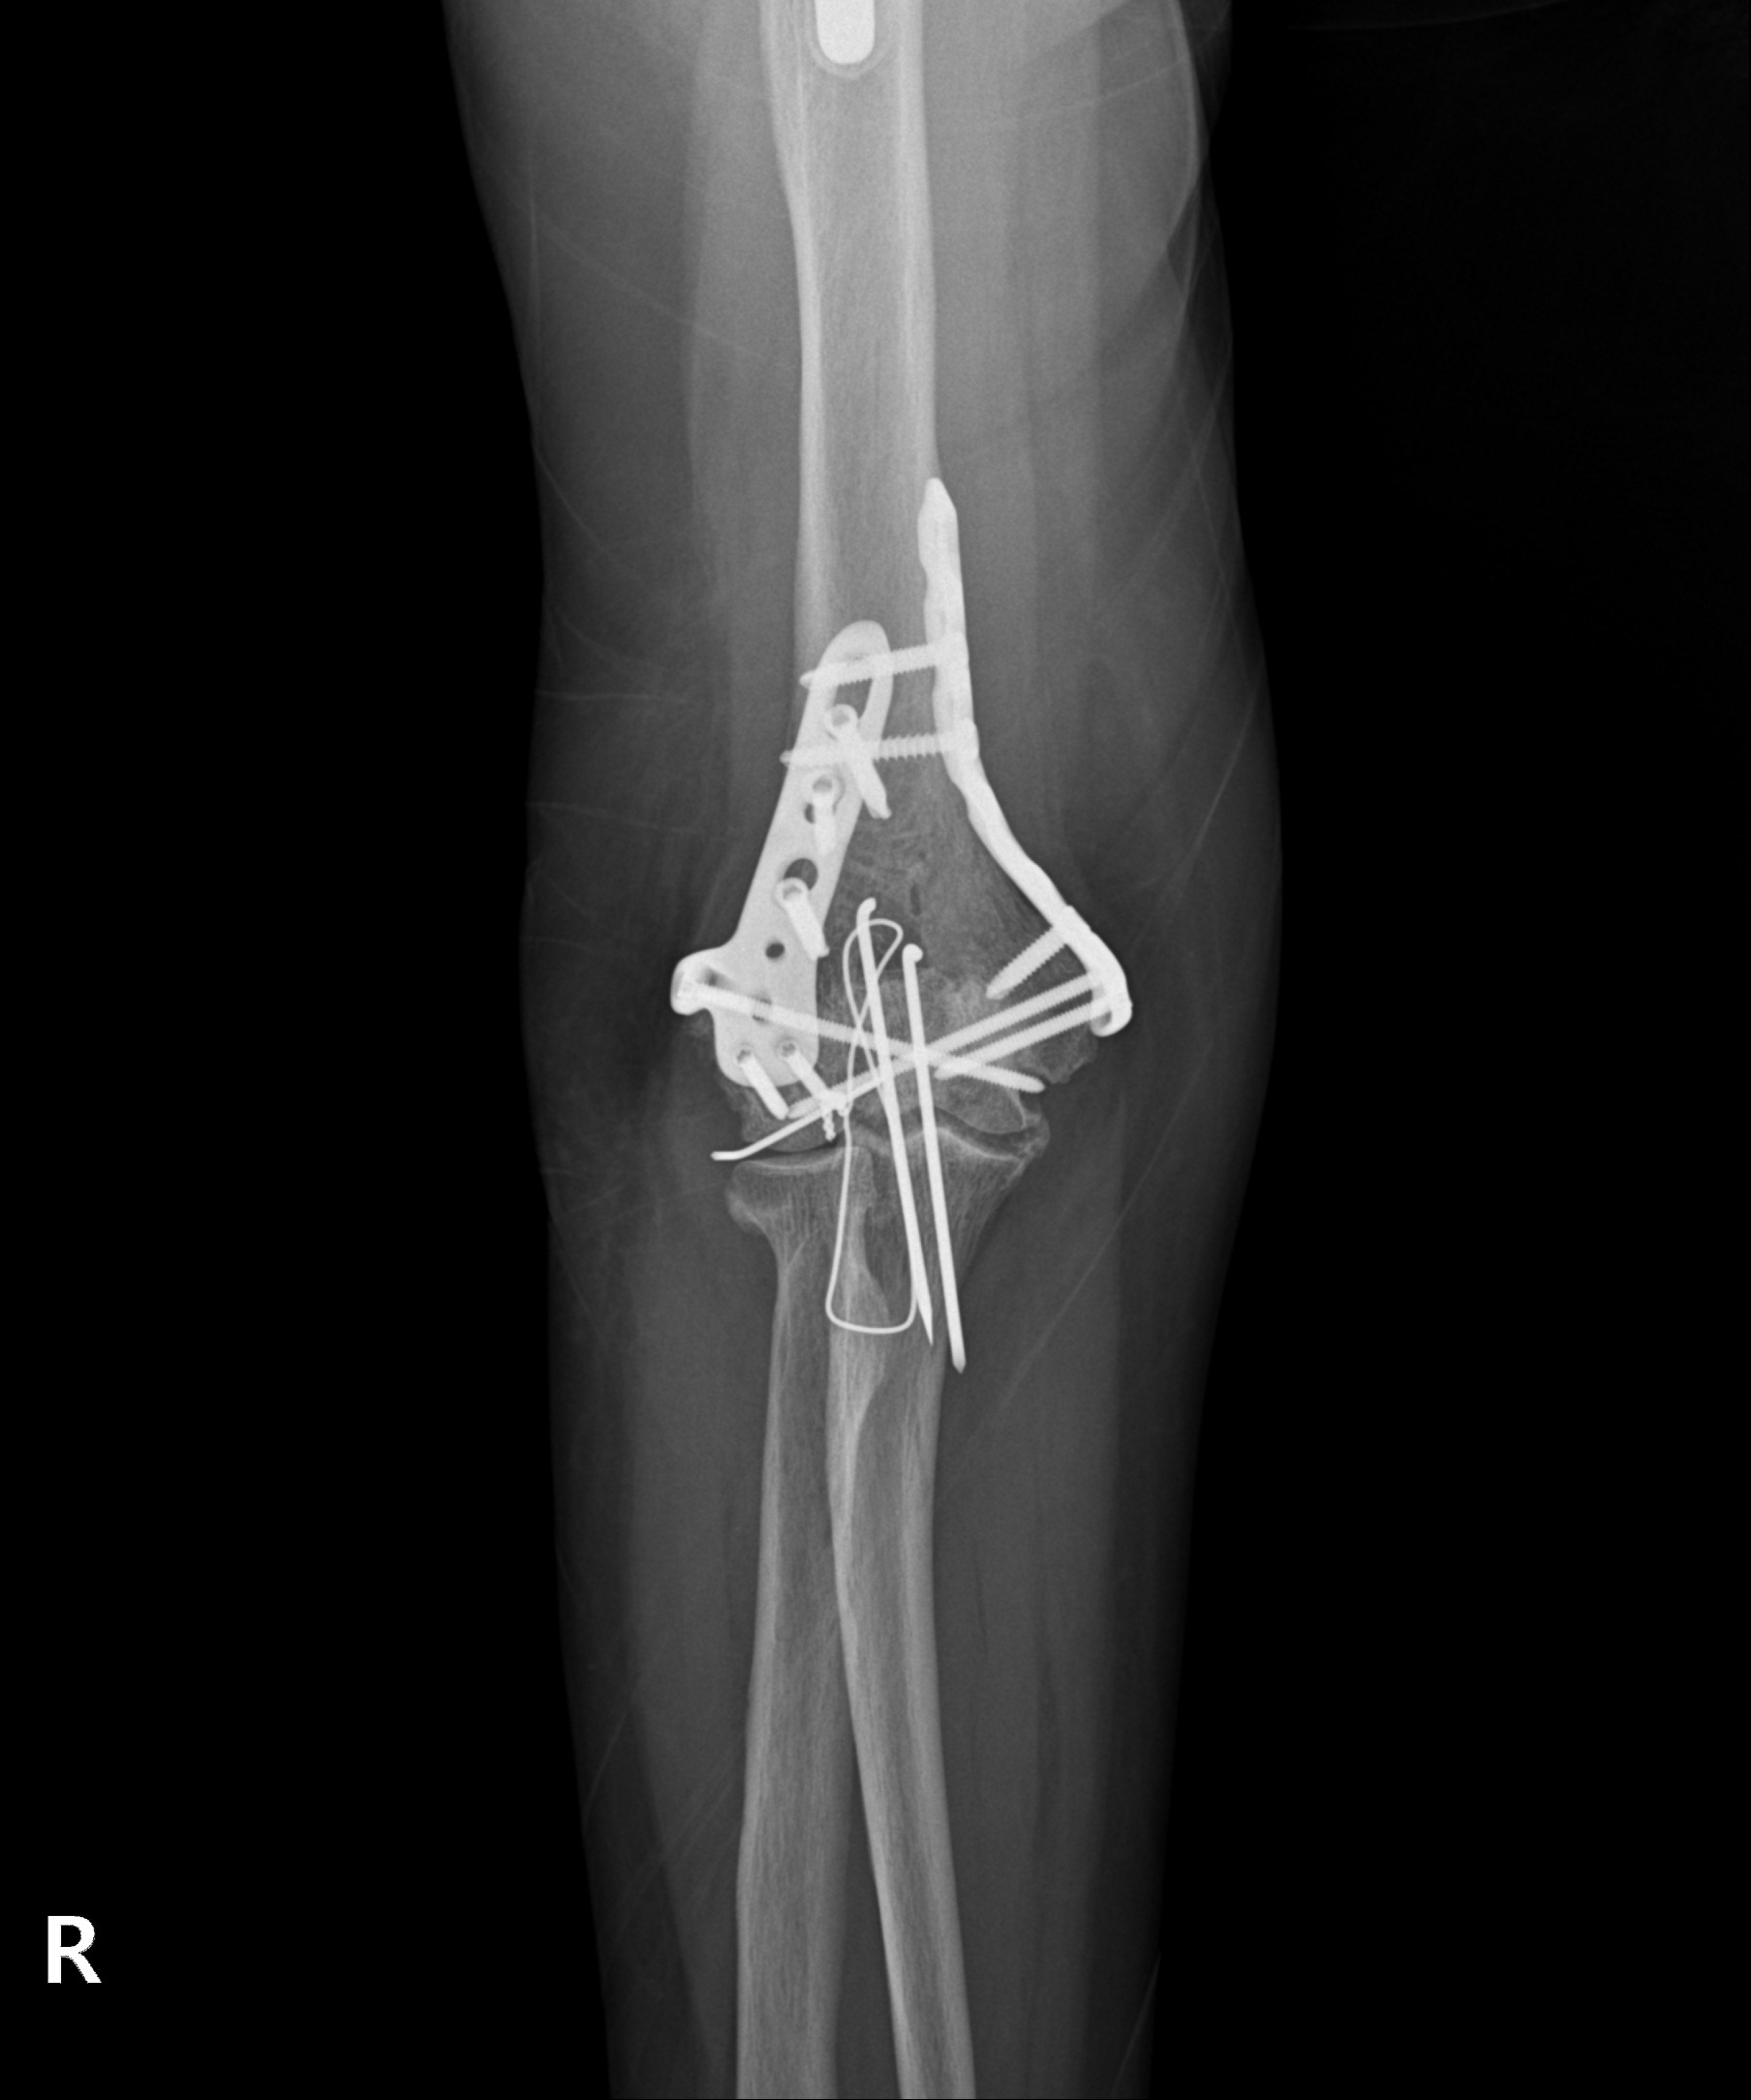

고난도 골절

2023.03.24

2023.03.31

원위 상완골 골절

2022.07.14

2023.02.07